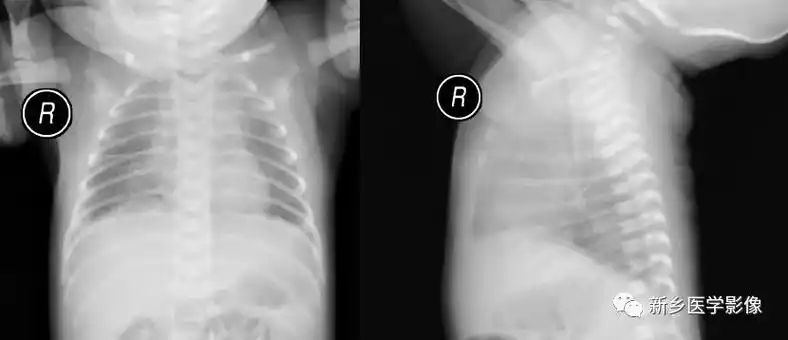

新生儿肺纹理粗不一定是肺炎,有可能是:新生儿湿肺

这几组患儿胸片是肺炎还是正常影像规培医师懵了